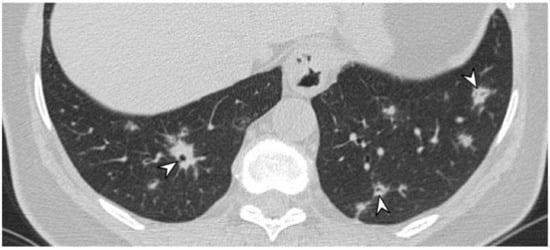

2.5. Eosinophilic Granulomatosis with Polyangiitis (EGPA-Churg-Strauss)

| EGPA | Migrant GGOs, transient consolidation, irregular bronchial wall thickening, small nodules with peribronchial and centrilobular distribution, pleural effusion. |